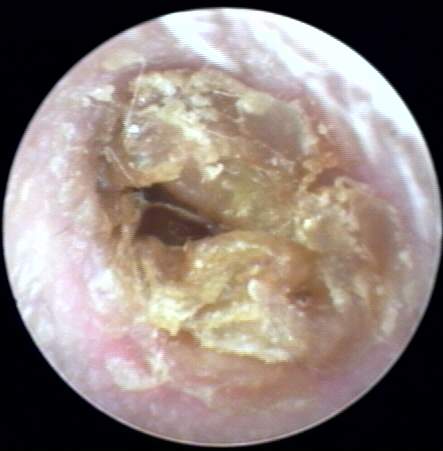

+1: Non-occlusive minor amount present but significant by location and texture to interfere with probe tube microphone measurements but not with ear-insert measurements [e.g. immittance or OAE] or hearing instrument use. Impact on impression-taking accuracy will vary with hearing instrument morphology; i.e. non-occluding full concha ITE vs. deep canal CIC. Tympanic membrane may be essentially visualized. Removal optional. EXAMPLES:+1/A(21k) | +1/B(22k) | +1/C(22k) | +1/D(18k)